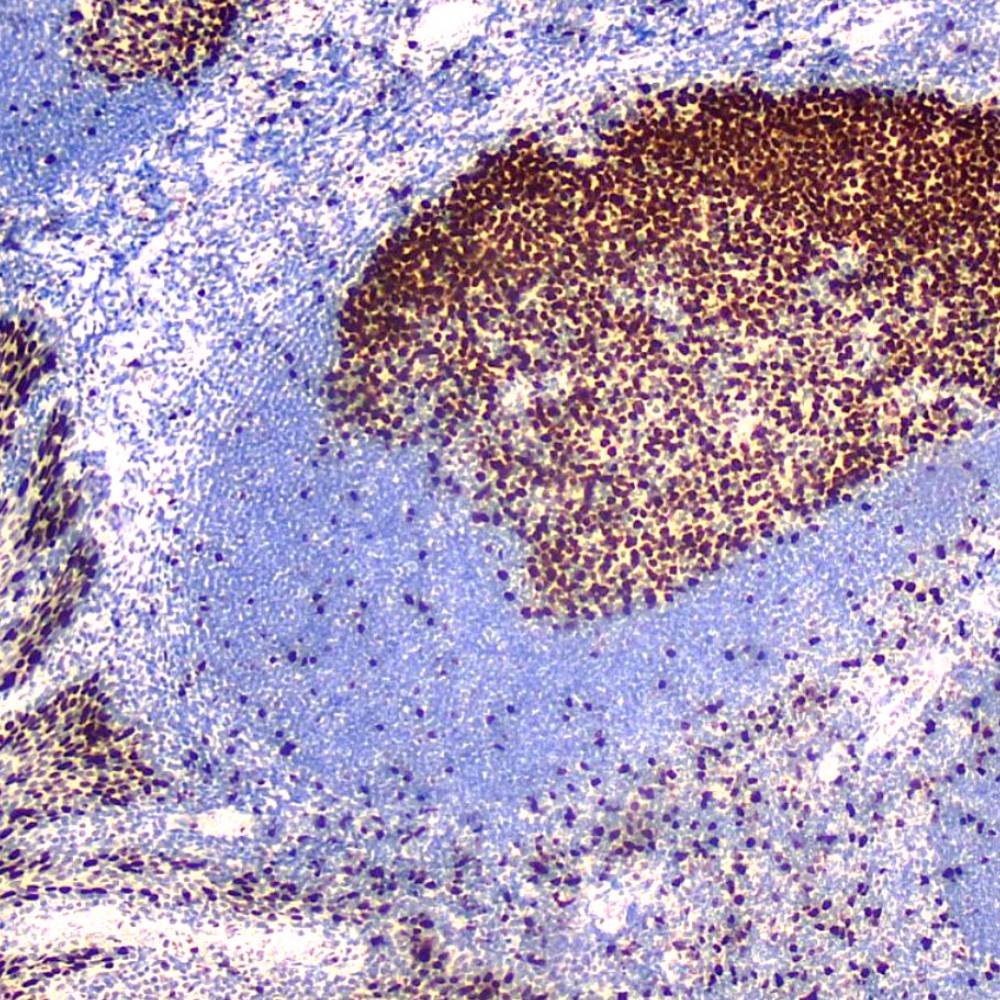

p40 antibody (antibody recognizing ΔNp63 only) is an isoform of p63, is thought to function as a stem cell factor, responsible for maintaining cells in an uncommitted state with regenerative potential—a role that may be recapitulated in tumors derived from these cells. p40 is normally expressed in the basal or progenitor cell layer of stratified epithelia (eg. squamous, urothelial, bronchial), basal cells of some glandular epithelia (eg. prostate), as well as myoepithelial cells of breast and salivary glands, trophoblasts and thymic epithelial cells. In tumor tissues, p40 expression is specific for squamous cell carcinoma. p40 is equivalent to p63 in sensitivity for lung squamous cell carcinoma, but it is markedly superior to p63 in specificity, which eliminates a potential pitfall of misinterpreting a p63-positive adenocarcinoma or unsuspected lymphoma as squamous cell carcinoma. p40 appears to be a more reliable marker for squamous cell carcinoma.

The rabbit monoclonal antibody p40 recognizes an epitope unique to the p40 protein and may have applications in cases where p63 has traditionally been used. p63 recognizes both the p63 and p40 proteins. As a result, p63 suffers from specificity limitations due to reactivity in a subset of lung adenocarcinomas (ADC). In contrast, p40 is selectively expressed in lung Squamous cell carcinoma (SqCC), offering an opportunity for improved specificity. p40 antibody recognizes an epitope unique to p40, which may result in diminished reactivity in lung ADC and increased specificity. Studies have supported routine use of p40 as an alternative for p63.